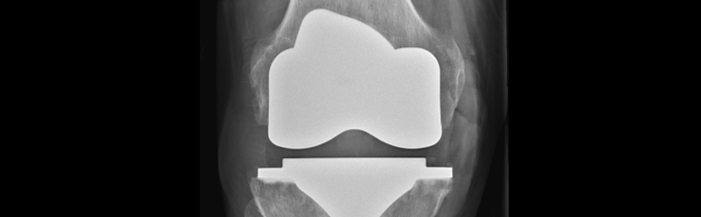

I Sverige utförs drygt 25 000 höftprotesoperationer och drygt 20 000 knäprotesoperationer årligen. De patienter som drabbas av protesrelaterade infektioner behöver mer vård, ofta lång tids antibiotikabehandling samt i vissa fall även reoperationer.